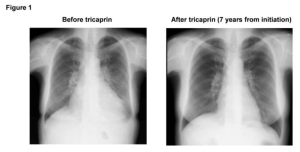

In a study published in Nature Cardiovascular Research, the research team found that tricaprin, a natural supplement, can improve long-term survival and recovery from heart failure in patients with triglyceride deposit cardiomyovasculopathy (TGCV).

“Not only did the positive effects on patient symptoms continue, but the function of the heart muscle improved and the structural changes that had developed were reversed as well,” says Hirano, the principal investigator for the Japan TGCV study group.

All the enrolled patients initially had heart failure; nevertheless, the three- and five-year survival rates were significantly higher in the tricaprin group (100% and 100%, respectively) compared with the control group (78.6% and 68.1%, respectively). Another favorable result was that several patients who had positive effects with tricaprin were on hemodialysis. These patients have a very poor prognosis without tricaprin.